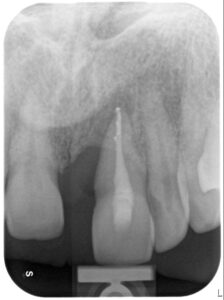

– tratament endodotic: pentru ca în interiorul dintelui nervul și vasele de sange era afectate, cu risc de infectie, s-a realizat tratamentul de canal.

– tratament parodontal chirurgical: din cauza faptului ca dintele modificat avea în jurul lui o distructie mare a osului, prin interventia chirurgicala s-a îndepartat gingia alterata care umplea acel defect osos altfel încat nu doar sa fie oprita distructia osului ci si sa stimuleze refacerea partiala o osului.

– tratamentul ortodontic: prin acesta dintele modificat se trage în jos prin miscari controlate de aparatul ortodontic iar dintele coborat în acest fel va trage dupa el, pe de o parte osul din profunzime si va creste nivelul și volumul sau, și pe altă parte, marginea gingiei care este nevoie sa ajungă la nivelul dintelui sanatos vecin pentru simetrie.